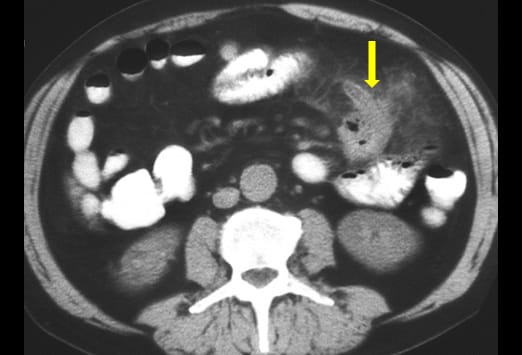

Die Abbildung auf der linken Seite zeigt eine einfache Appendizitis. Hier ist eine Verbreiterung und ein Ödem der Appendix zu sehen, mit einer erhöhten Kontrastmittelaufnahme der Appendixwand (blauer Pfeil) und einer geringen umgebenden Entzündungsreaktion. Beim Fortschreiten einer Appendizitis kommt es von der einfachen Form und einer nachfolgenden gangränösen Veränderung schließlich zur Perforation. Nach der initialen Obstruktion des Lumens kann es zu einer verminderten Perfusion kommen. Das Bild auf der rechten Seite zeigt eine gangränöse Appendizitis, bei welcher es zu einer Zunahme und einer Infiltration in das Mesenterium gekommen ist. Ein Appendikolith (gelber Pfeil) kommt ebenfalls zur Darstellung.